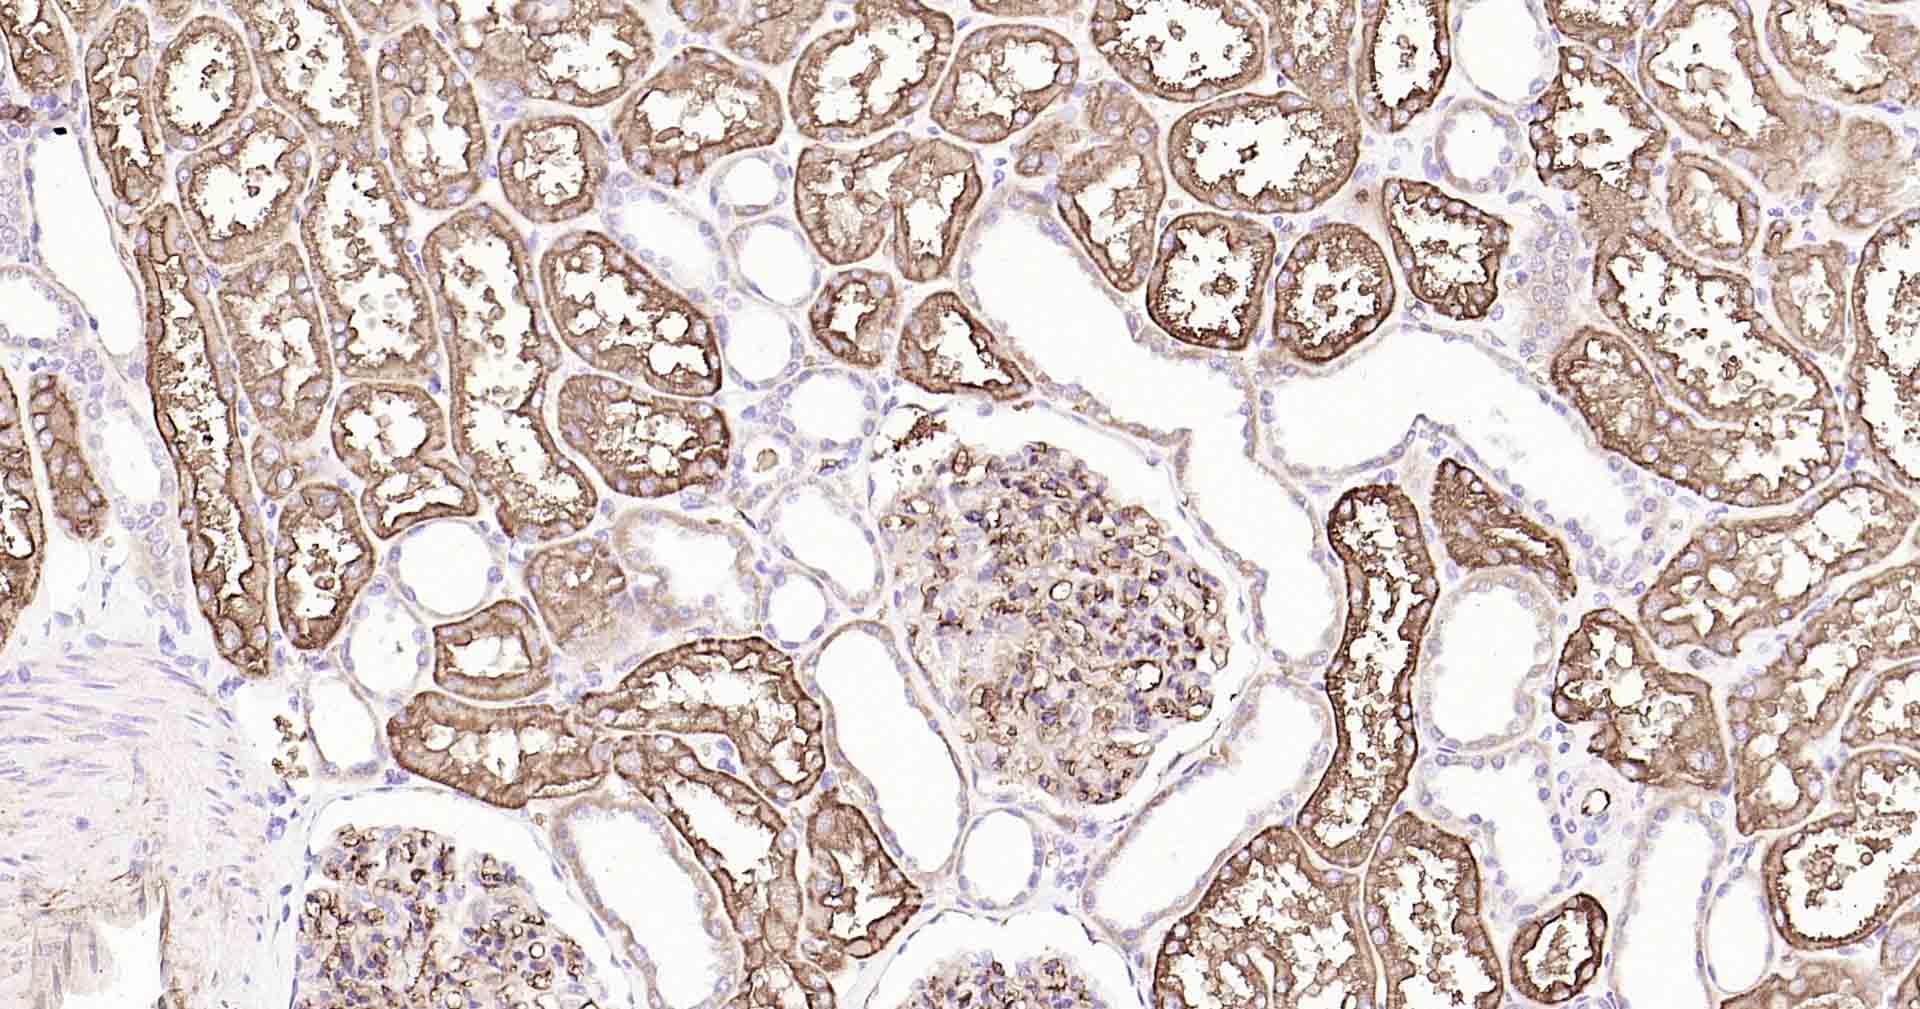

Paraformaldehyde-fixed, paraffin embedded Human Kidney; Antigen retrieval by boiling in sodium citrate buffer (pH6.0) for 15 min; Antibody incubation with AQP1 Monoclonal Antibody, Unconjugated(bsm-52909R) at 1:200 overnight at 4°C, followed by conjugation to the SP Kit(Rabbit, SP-0023) and DAB (C-0010) staining.

Paraformaldehyde-fixed, paraffin embedded Rat Kidney; Antigen retrieval by boiling in sodium citrate buffer (pH6.0) for 15 min; Antibody incubation with AQP1 Monoclonal Antibody, Unconjugated(bsm-52909R) at 1:200 overnight at 4°C, followed by conjugation to the SP Kit(Rabbit, SP-0023) and DAB (C-0010) staining.

Paraformaldehyde-fixed, paraffin embedded Mouse Kidney; Antigen retrieval by boiling in sodium citrate buffer (pH6.0) for 15 min; Antibody incubation with AQP1 Monoclonal Antibody, Unconjugated(bsm-52909R) at 1:200 overnight at 4°C, followed by conjugation to the SP Kit(Rabbit, SP-0023) and DAB (C-0010) staining.